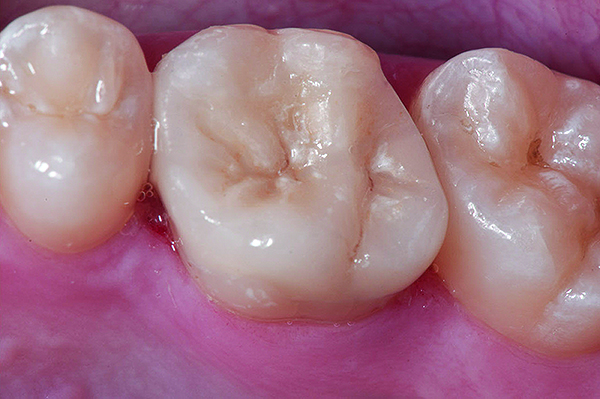

Figure 9 Preoperative preparation with composite block-out restoration, final cementation of Class IIb material, and final ceramic contour and stain by Steve Lee, CDT, MDC.

Figure 9

Figure 10 Preoperative preparation with composite block-out restoration, final cementation of Class IIb material, and final ceramic contour and stain by Steve Lee, CDT, MDC.

Figure 10

Figure 11 Preoperative preparation with composite block-out restoration, final cementation of Class IIb material, and final ceramic contour and stain by Steve Lee, CDT, MDC.

Figure 11